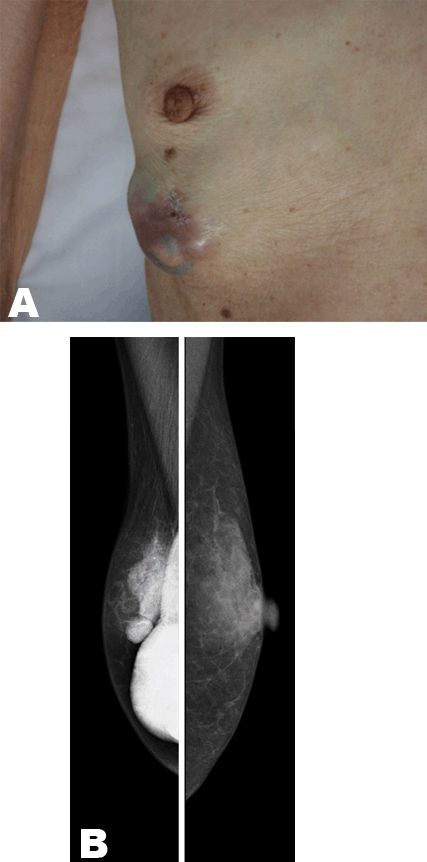

A 78-year-old Japanese postmenopausal woman presented with a large right breast mass four months prior to admission (Figure 1A). Physical examination revealed one 5.0x5.0 cm palpable cystic mass that was elastically firm in the lower external quadrant of the right breast. There was no abnormal nipple discharge. Mammography revealed a well-defined large dense mass (Figure 1B). Sonography revealed a well-demarcated intracystic tumor with papillary growth in the right breast (Figure 2A), and MRI scan showed an intracystic mass with a papillary lesion, indicating invasion (Figure 2B). There was no evidence of axillary lymphadenopathy. A biopsy had been performed at the previous hospital and revealed an invasive ductal carcinoma. Breast conservative surgery with sentinel lymph node (SLN) biopsy was performed, and a white intracystic papillary tumor was removed (Figure 2C). During surgery, an axillary SLN was detected with blue dye and a hot (radioactive) tracer. Briefly, twelve hours prior to surgery, the radioisotope with 99mTc-phytate colloid was injected subcutaneously in the periareolar region. Intradermal injection of a blue dye, indigo carmine, in the periareolar region was also performed immediately prior to surgery. Any lymph nodes with blue dye and radioactivity were regarded as SLN [11] [12] [13]. The intraoperative diagnosis of SLN was positive for metastasis, and additional conventional axillary lymph node dissection (ALND) was therefore performed. At final histology, none of the non-SLN was metastatic. Histological evaluation revealed a lesion containing papillary structure in the cystic space and a solid tubular carcinoma with invasion to the outside of the cyst wall that had been detected by preoperative MRI. These findings are compatible with intracystic papillary carcinoma associated with invasive ductal carcinoma (Figure 3). Immunohistochemical staining showed estrogen and progesterone receptor were positive and the patient's HER2 score was 0. The patient has not received adjuvant therapy or radiotherapy because of severe dementia. The patient has remained alive for 14 months without locoregional or systemic recurrence of the tumor.

Figure 1: (A) A 5.0x5.0 cm palpable cystic mass was elastically firm in the lower external quadrant of the right breast, and (B) Mammography revealed a well-defined large dense mass.